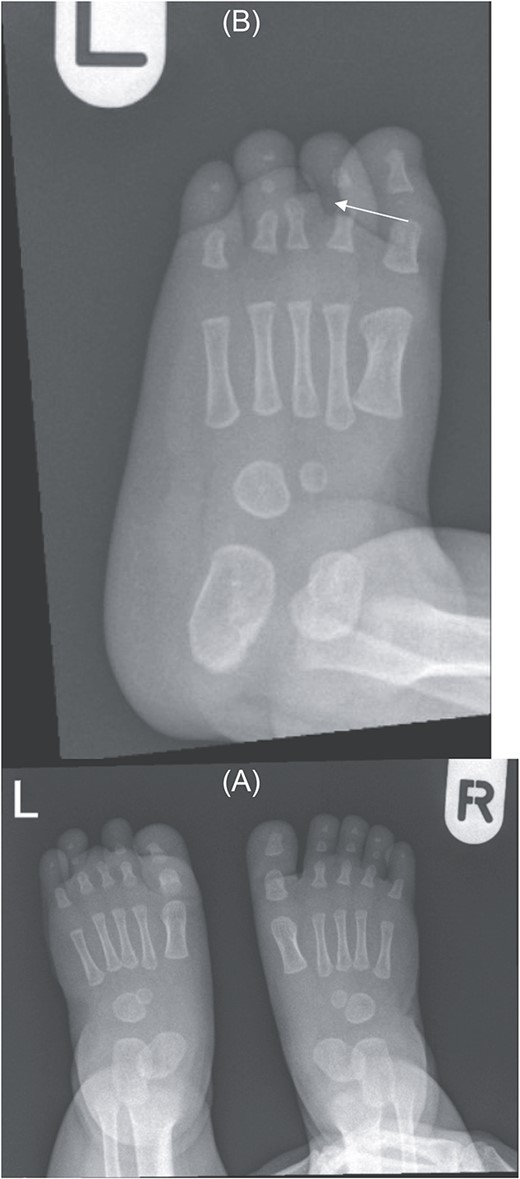

Foot X-ray confirms hypoplastic left third toe with no visualization of middle and distal phalanges — suggesting a very rare variant of brachydactyly (type B) (Fig. 2).

(A) Bilateral feet X-ray with normal right foot bone anatomy and left foot X ray. (B) No visualization of third toe middle and distal phalanges (arrow).